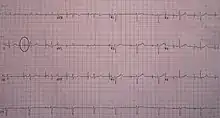

Transcutaneous pacing (TCP), also called external pacing, is recommended for the initial stabilization of hemodynamically significant bradycardias of all types. The procedure is performed by placing two pacing pads on the patient's chest, either in the anterior/lateral position or the anterior/posterior position. The rescuer selects the pacing rate, and gradually increases the pacing current (measured in mA) until electrical capture (characterized by a wide QRS complex with a tall, broad T wave on the ECG) is achieved, with a corresponding pulse. Pacing artifact on the ECG and severe muscle twitching may make this determination difficult. External pacing should not be relied upon for an extended period of time. It is an emergency procedure that acts as a bridge until transvenous pacing or other therapies can be applied.[8]